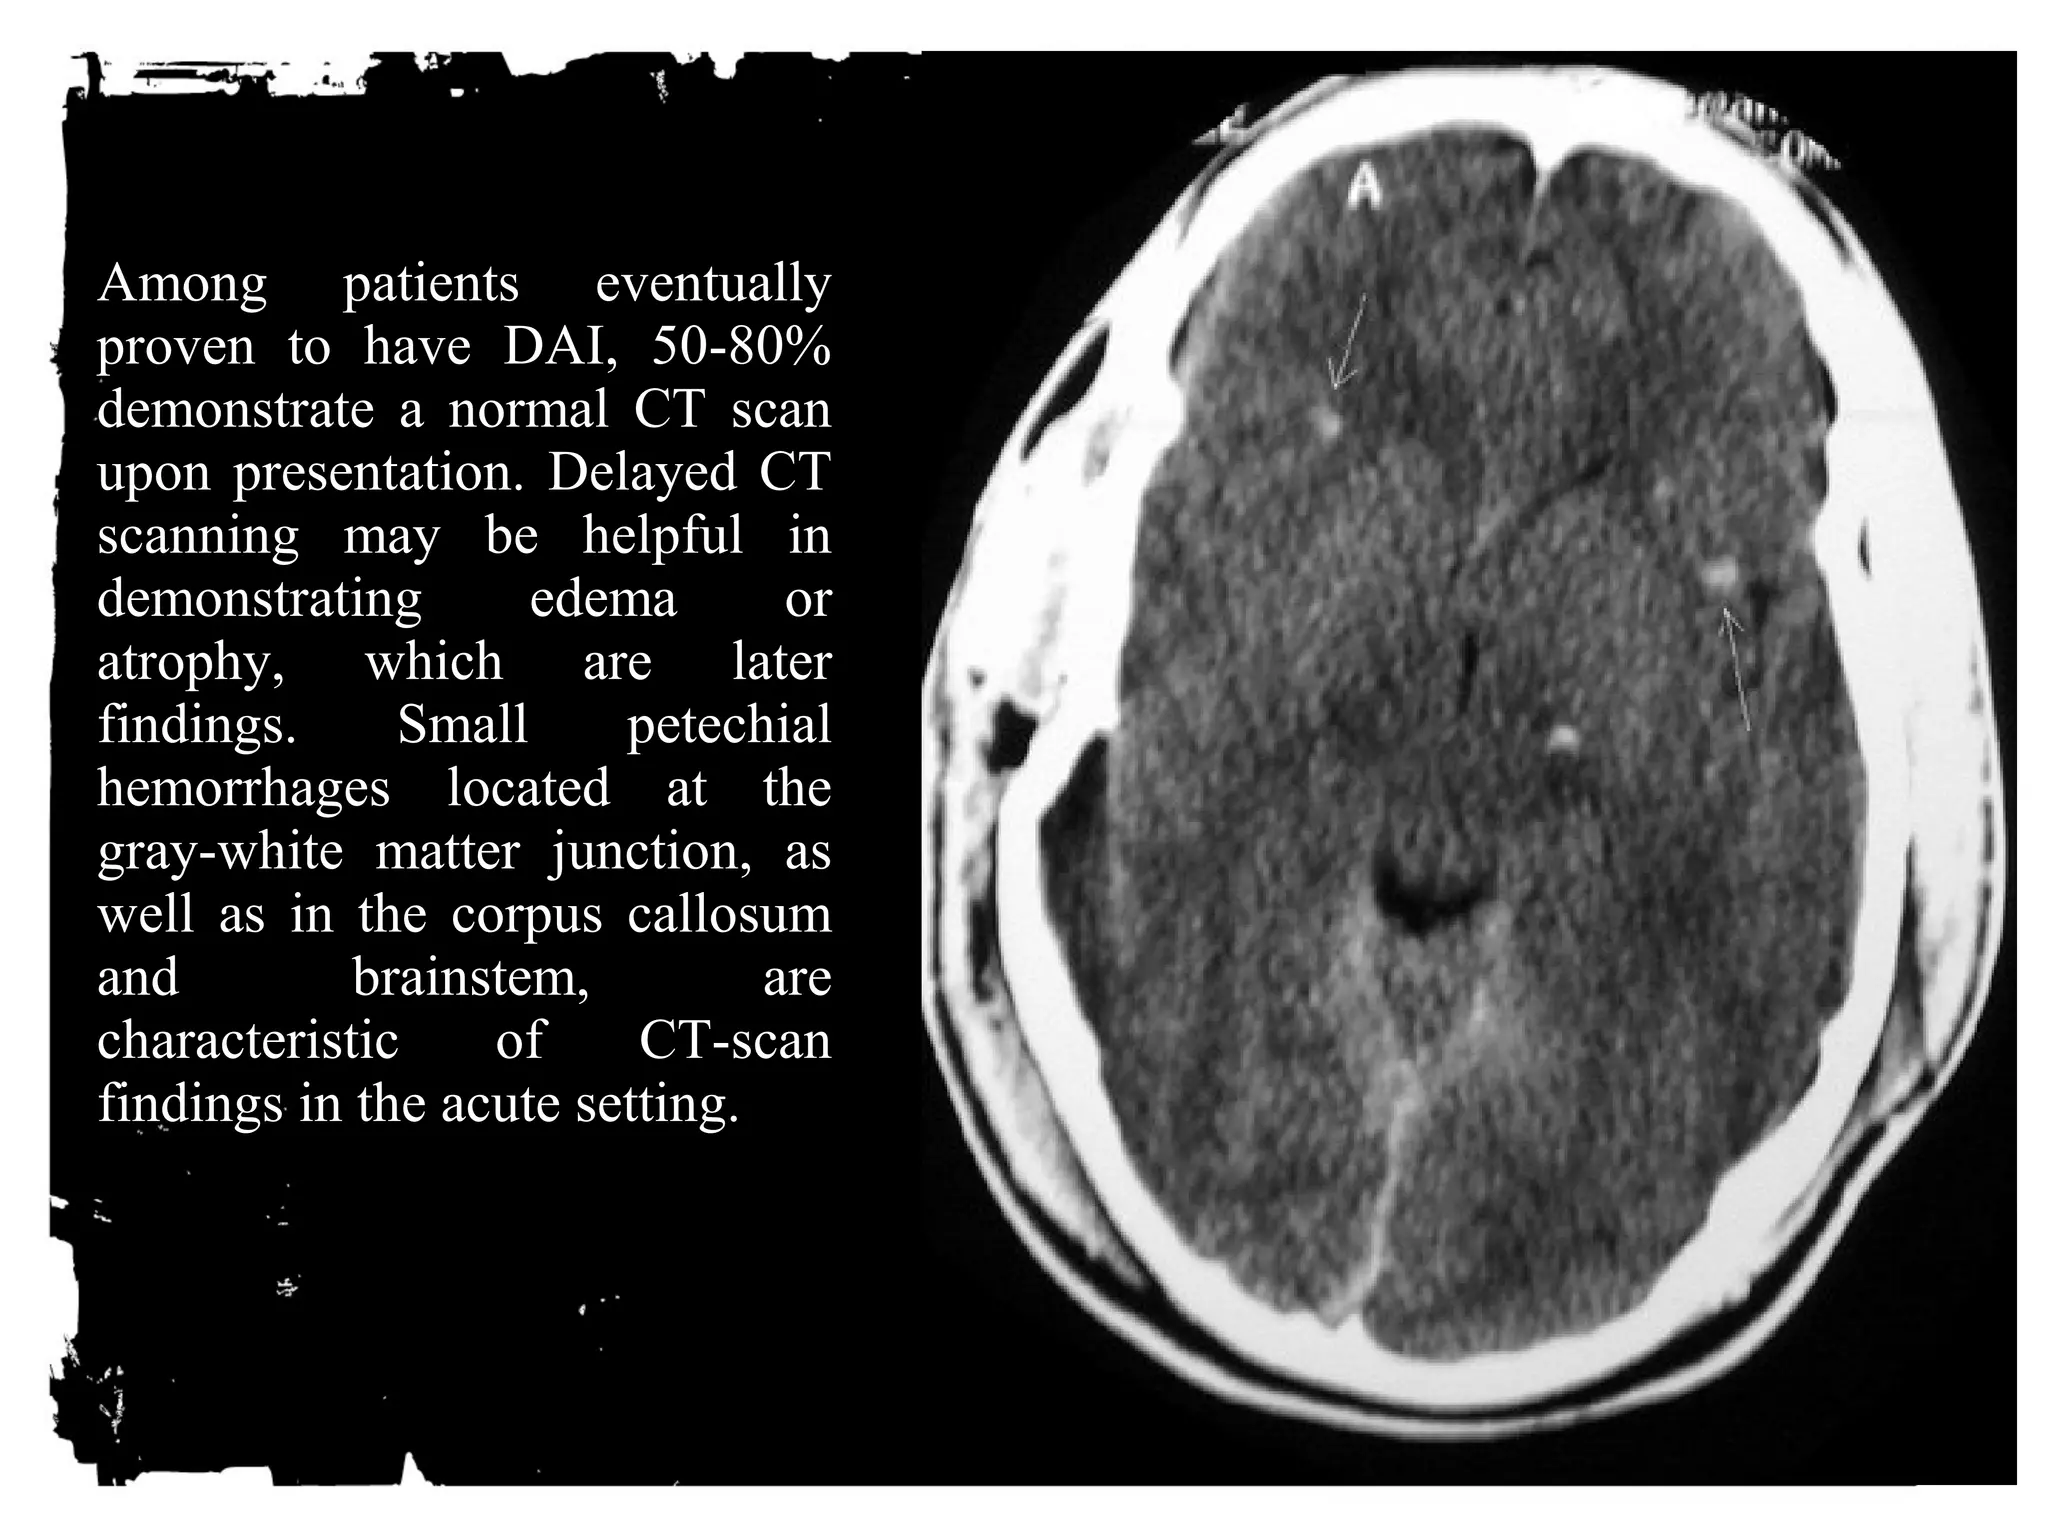

Diffuse axonal injury

Diffuse axonal injury (DAI) is a major form of traumatic

brain injury and is caused by shearing stress primarily in

white matter). Various outcomes are reported (ie, learning

Among patients eventually

proven to have DAI, 50-80%

demonstrate a normal CT scan

upon presentation. Delayed CT

scanning may be helpful in

demonstrating edema or

atrophy, which are later

findings. Small petechial

hemorrhages located at the

gray-white matter junction, as

well as in the corpus callosum

and brainstem, are

characteristic of CT-scan

findings in the acute setting.